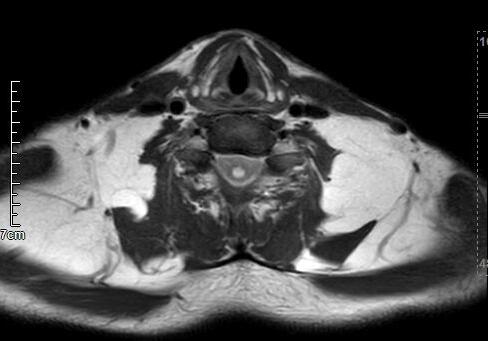

马德龙病的影像表现为颈项部等处脂肪组织蓄积增厚,可累及皮下或肌肉间隙,脂肪蓄积处没有包膜形成,蓄积脂肪内可有线状或网状纤维间隔,病变常常左右对称,颈部肌肉可受压、变细,蓄积脂肪组织内可有钙化或骨化。

刀某颈部MRI